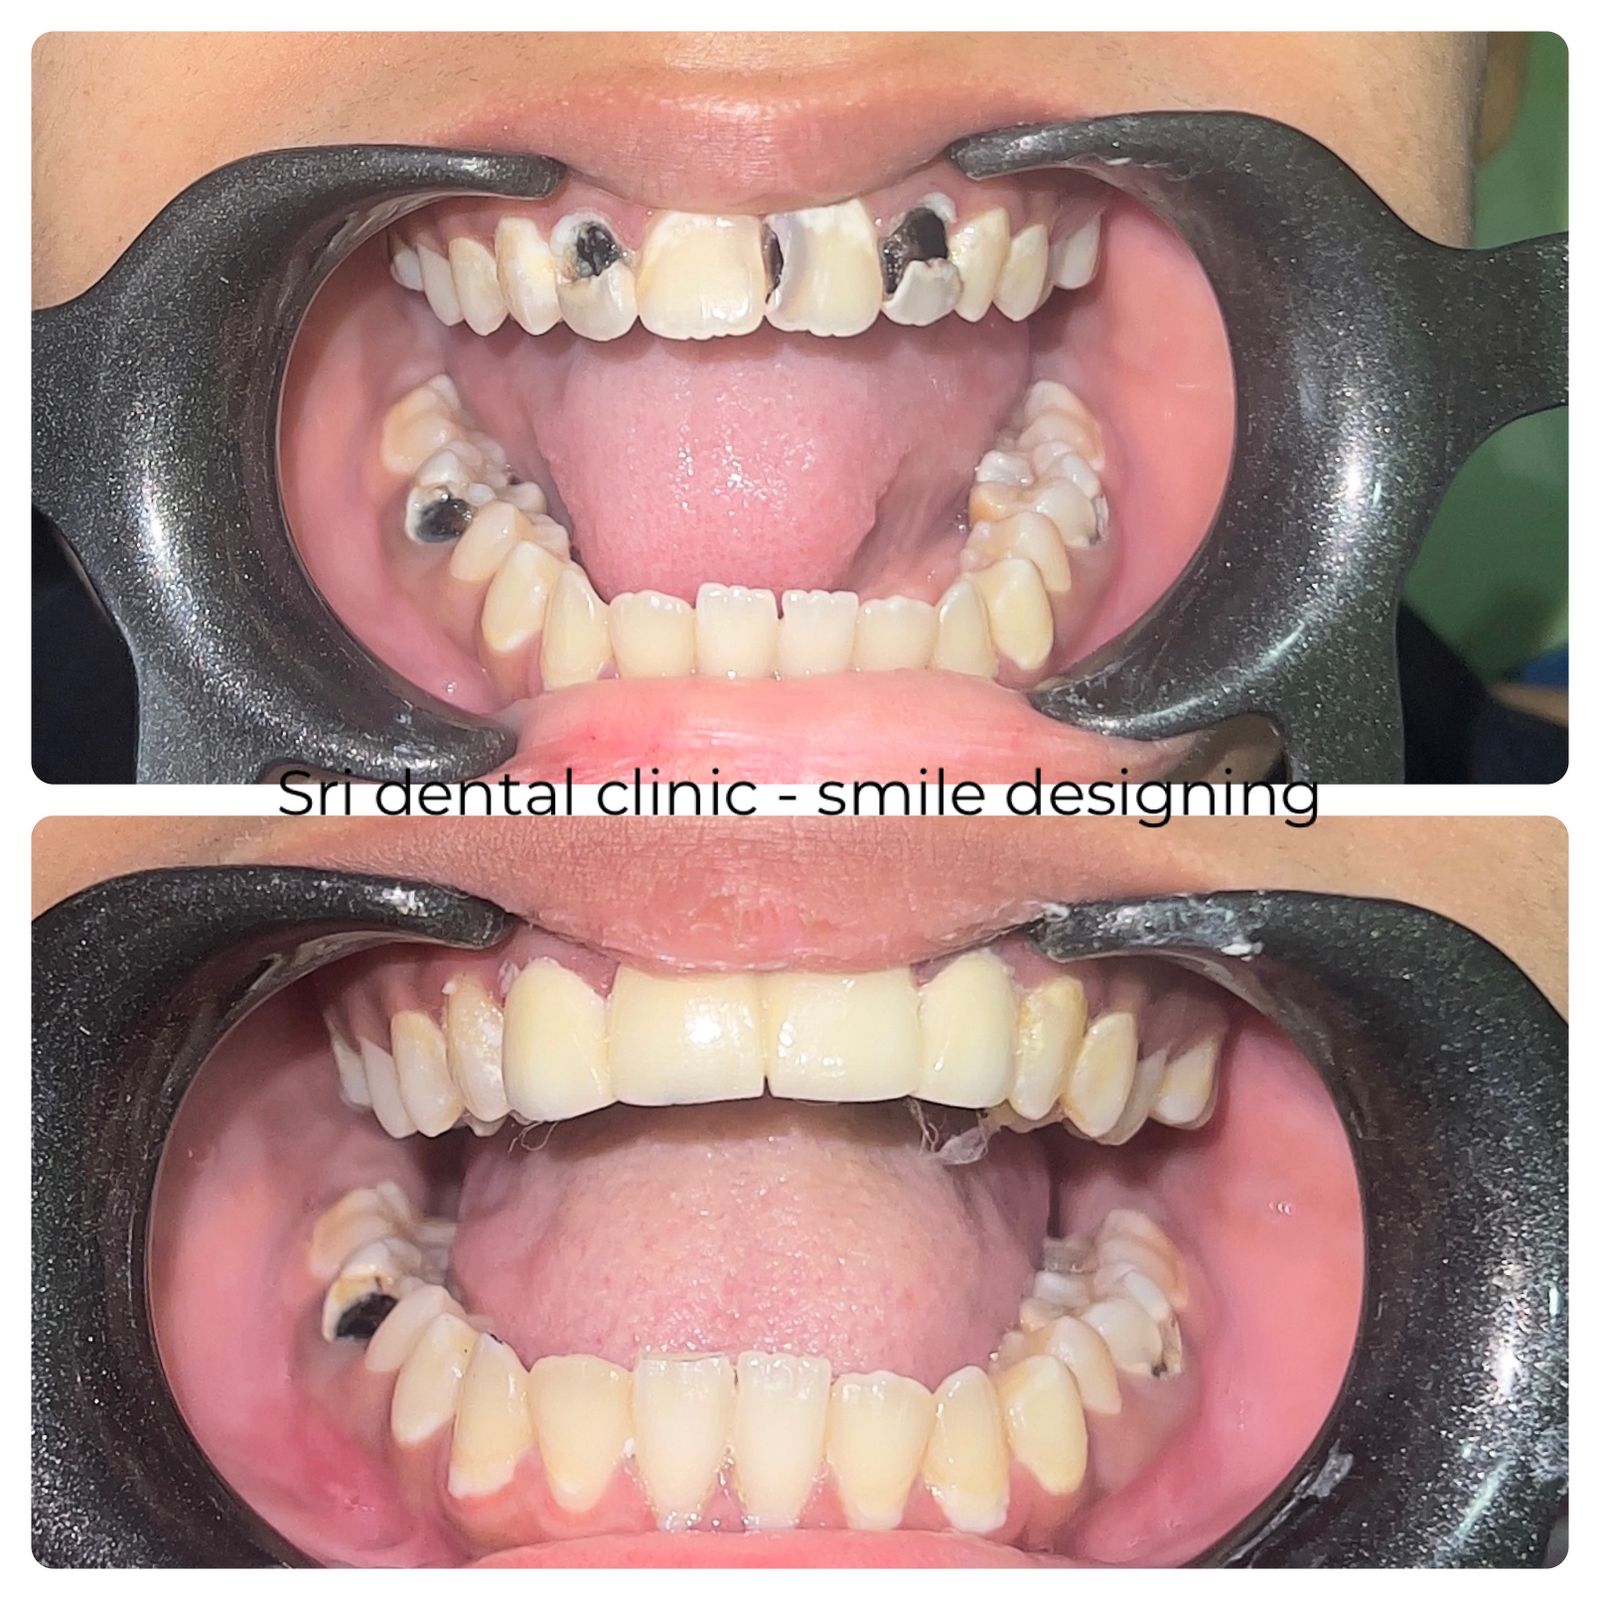

Prosthetics:

Dental Prosthetics restore lost or damaged teeth to improve oral function, aesthetics, and overall dental health.

Types of Dental Prosthetics We Offer

Crowns

A crown is a tooth-shaped cap placed over a weak or root-canal-treated tooth to restore its shape, strength, and appearance.

Bridges

Bridges fill the space created by one or more missing teeth, using adjacent teeth as support.